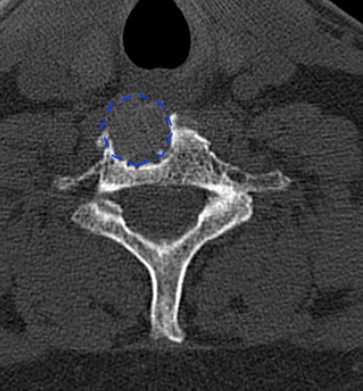

Obsérvese la ubicación de la prótesis

La flecha azul indica el hundimiento/resorción del platillo C7 en lado derecho, (la prótesis se ubicó muy lateral); el lado izquierdo (flecha roja) parece íntegro.